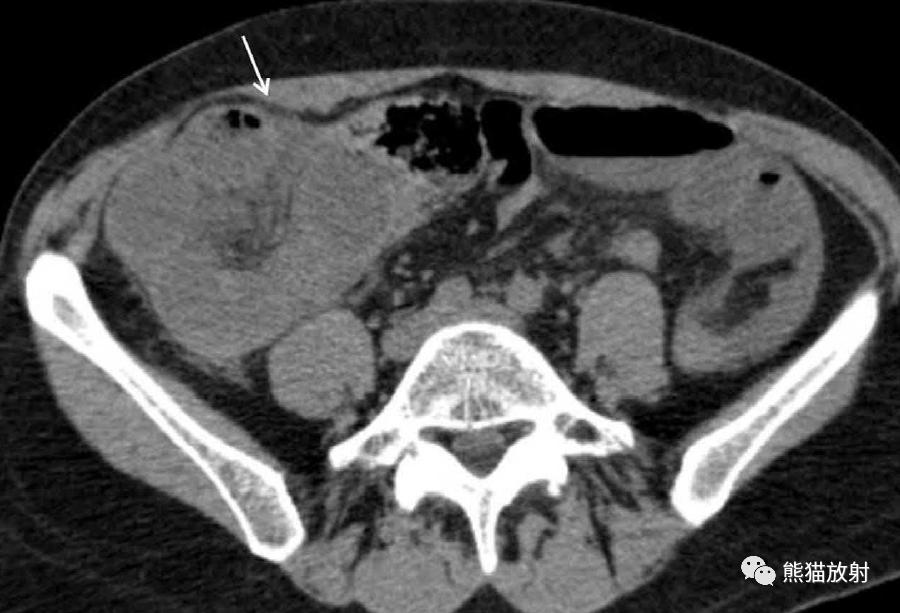

3、肠系膜囊肿

淋巴管瘤是最常见的肠系膜囊性病变;

肠重复囊肿、肠囊肿、间皮囊肿比较罕见。

肠系膜囊性淋巴管瘤 。增强CT示右腹部多房囊性肿块,可见菲薄分隔,占据小肠系膜。